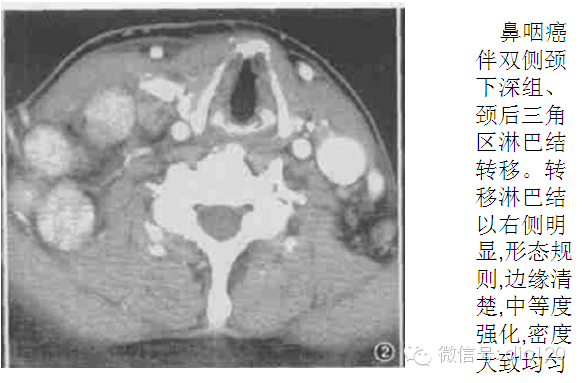

转移淋巴结发生部位和原发肿瘤的淋巴引流区域相关,口腔癌淋巴结转移主要发生于Ⅰ、Ⅱ、Ⅲ区,而口咽癌、下咽癌和喉癌主要发生Ⅱ、Ⅲ区.鼻咽癌转移淋巴结多为双侧发生,除常见于Ⅱ、Ⅲ、Ⅳ区外,咽后组、颈后三角区为鼻咽癌淋巴结转移的特征性部位,这与其他部位原发肿瘤有极显著性差异 。故咽后组淋巴结肿大时,应首先考虑鼻咽癌可能,若同时伴有颈后三角区淋巴结肿大,则诊断准确性更高,但需与淋巴瘤鉴别。

转移淋巴结形态及边缘

表现为形态规则且边缘清楚与形态不规则且边缘不清楚者,其原发肿瘤之间存在极显著性差异 。鼻咽癌及甲状腺癌中,形态规则且边缘清楚者分别为 88 % 和 86 % 。口咽癌,喉癌及下咽癌中形态不规则且边缘不清者分别为59 % 和68 % , 且外侵明显。这与口咽癌、下咽癌及喉癌分化差, 恶性程度高有关。